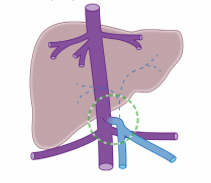

小贴士:先天性门体静脉分流是一种门静脉和体静脉之间存在异常交通的罕见先天性血管畸形,新生儿期的发病率约为 1/30000。根据分流位于肝脏内还是肝脏外,分为肝内型和肝外型。肝外型也叫Abernethy畸形,根据是否存在肝内门静脉又分为Ⅰ型和Ⅱ型,Ⅰ型为肝内门静脉完全缺如,门静脉血直接进入下腔静脉;Ⅱ型为肝内存在发育不良的门静脉,有一定程度的门静脉血入肝。患儿可出现肝功能受损和代谢异常、肺动脉高压、肝肺综合征、肝性脑病、肝脏肿瘤等表现。肝内型门体静脉分流有部分患儿可自愈,肝外型多需要手术治疗。

先天性门体静脉分流示意图(Abernethy Ⅰ型)